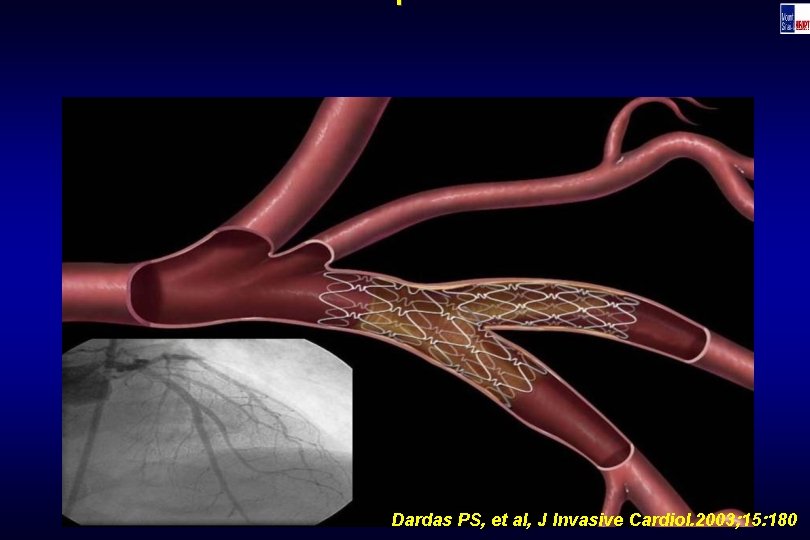

Technique Dardas PS, et al, J Invasive Cardiol. 2003; 15: 180

Technique Dardas PS, et al, J Invasive Cardiol. 2003; 15: 180

Technique Dardas PS, et al, J Invasive Cardiol. 2003; 15: 180

Technique Dardas PS, et al, J Invasive Cardiol. 2003; 15: 180

Technique Dardas PS, et al, J Invasive Cardiol. 2003; 15: 180

Technique Dardas PS, et al, J Invasive Cardiol. 2003; 15: 180